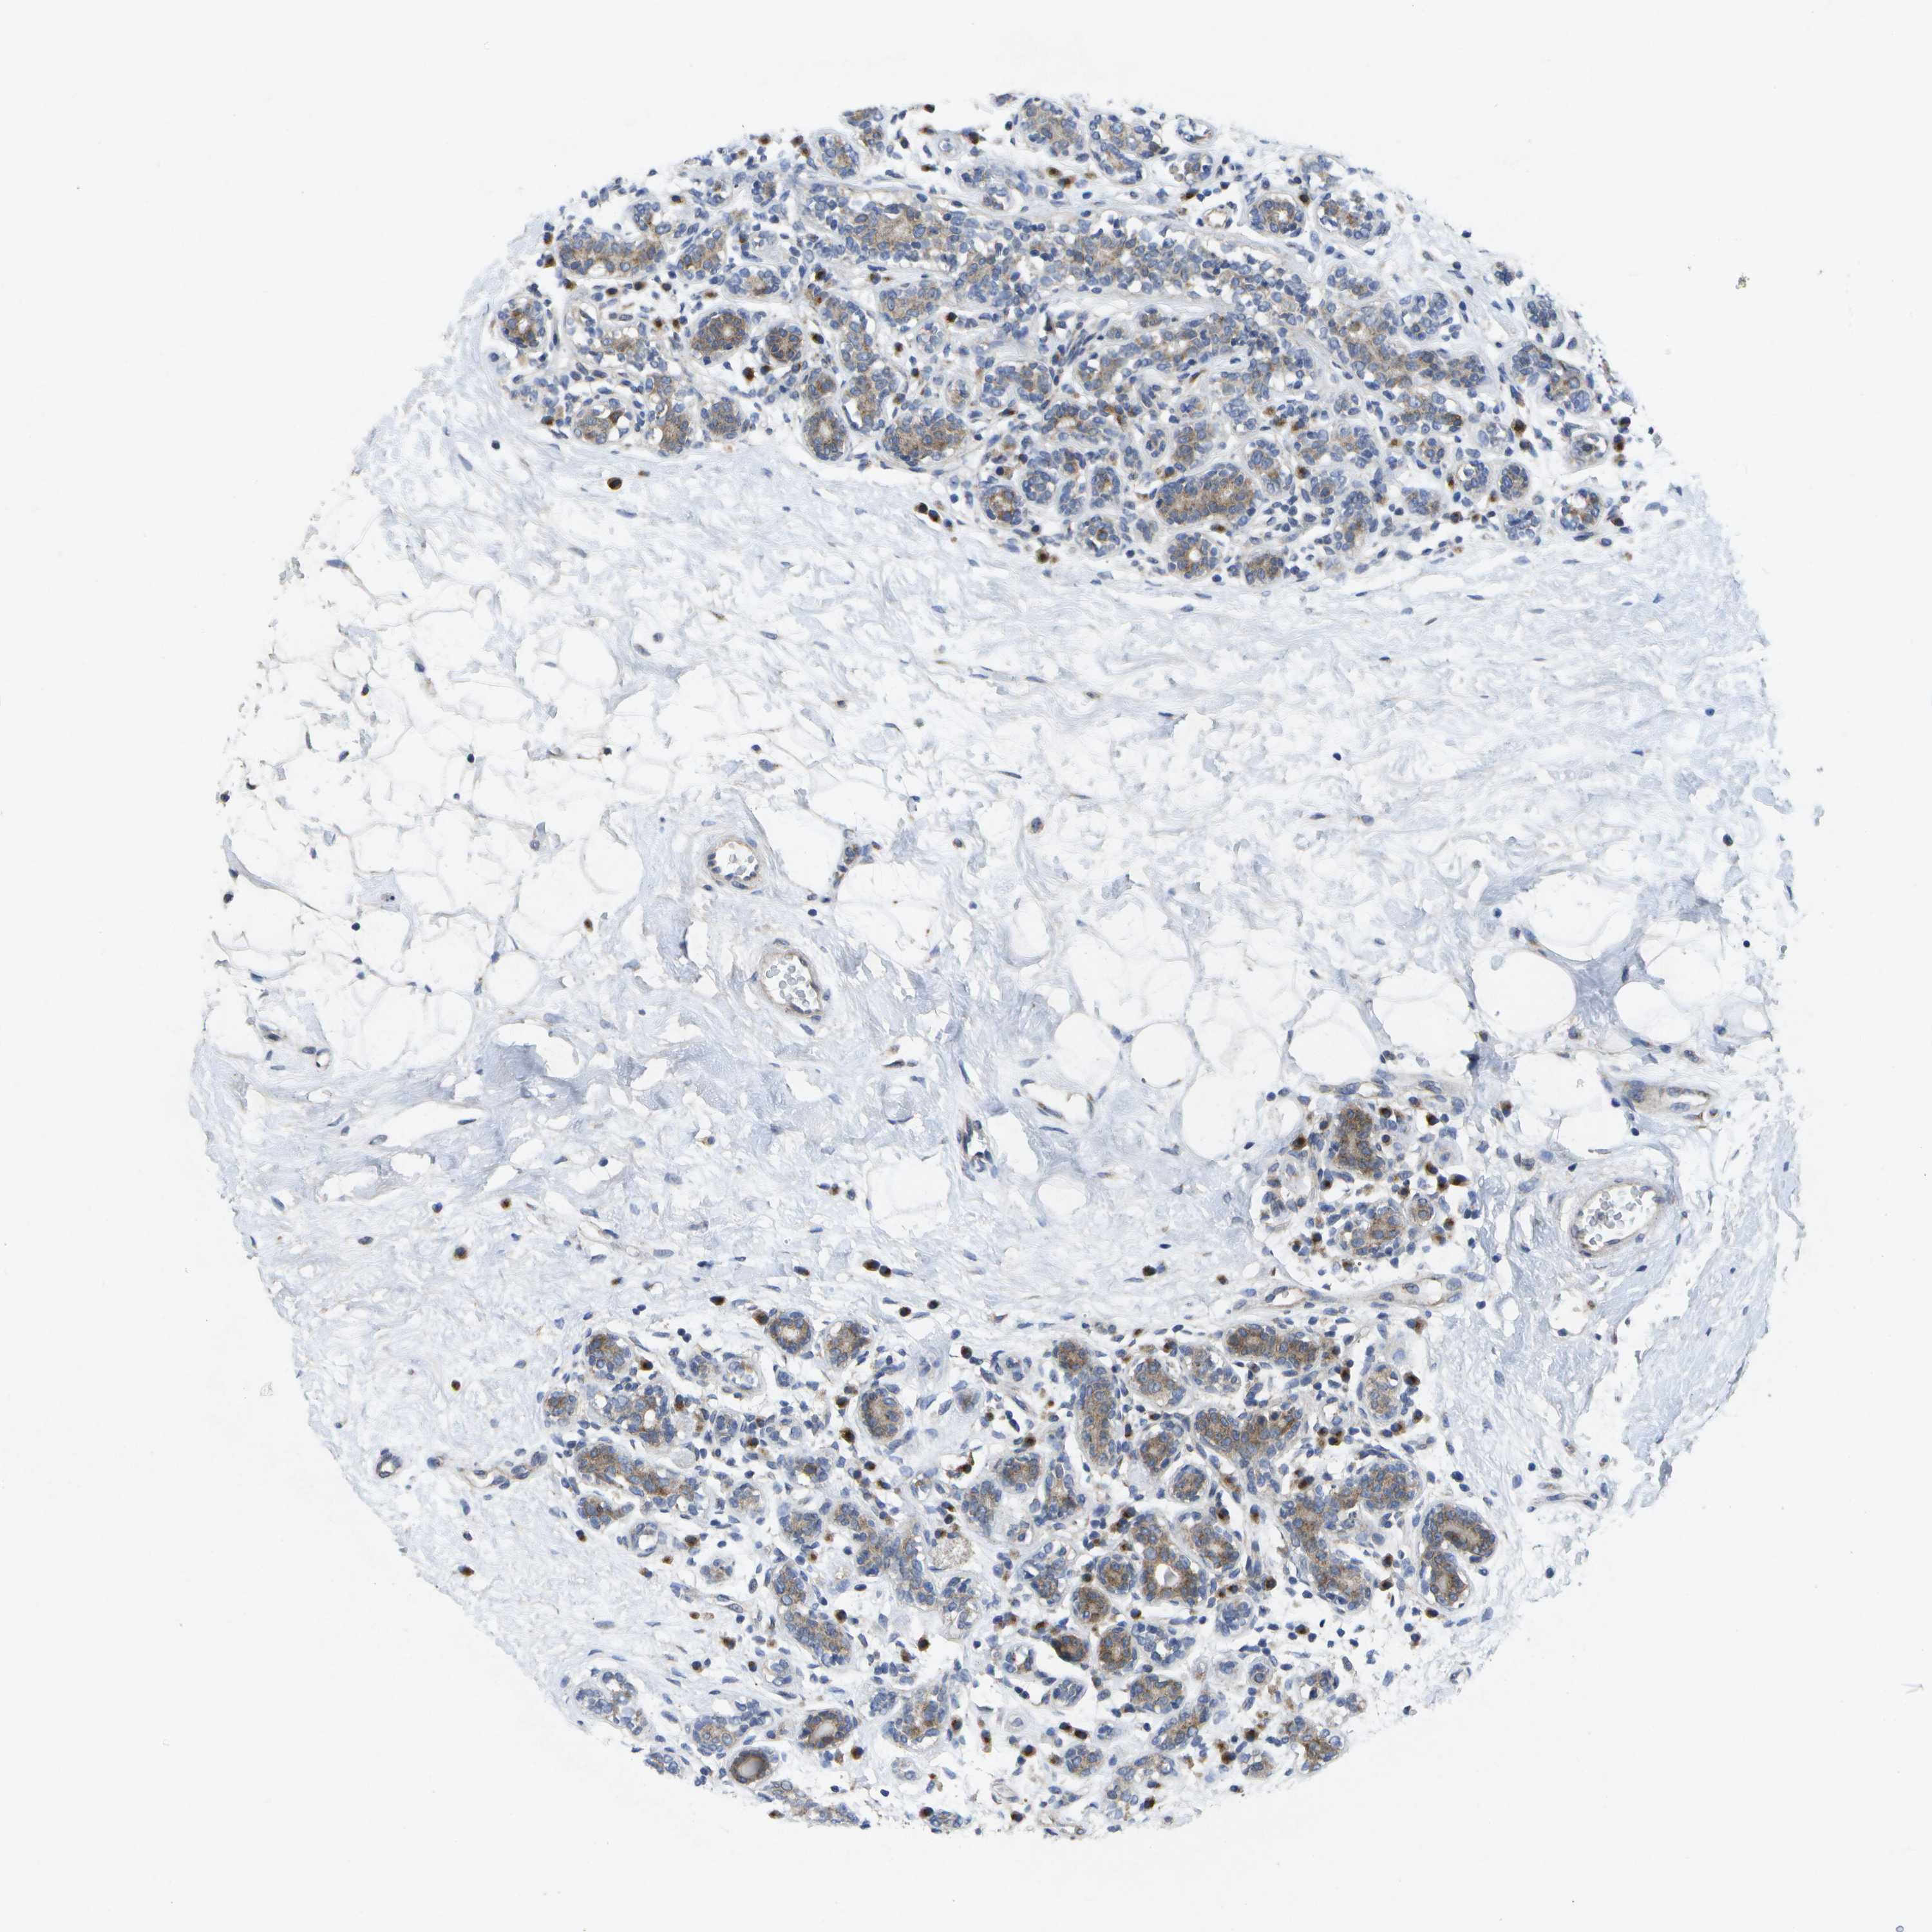

BRCA TCGA BRCA VALIDATION PROTEIN EXPRESSION